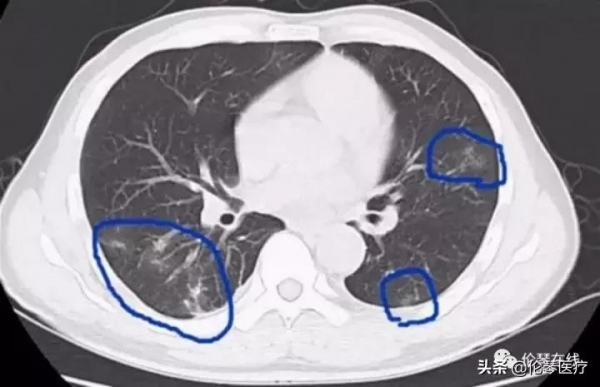

3、纖維瘢痕期,並殖囊腫內的蟲體死亡或移往別處,囊腫內及周邊的肉芽組織和纖維取代,形成瘢痕。CT表現為囊腫逐漸吸收,周圍紊亂的纖維條索或結節找,隨訪無變化。偶可見鈣化。胸膜侵犯亦很常見,胸膜增厚,特別是常見侷限性胸膜增厚。胸腔積液甚至早於肺內改變。具有特徵性的表現是雙側胸腔交替性積液,即一側胸水減少或吸收後出現對側胸水,少數病例有多次交替或同時出現胸水。心包增厚或心包少量積液亦可見。

雙肺斑片狀滲出,並可見小囊狀影